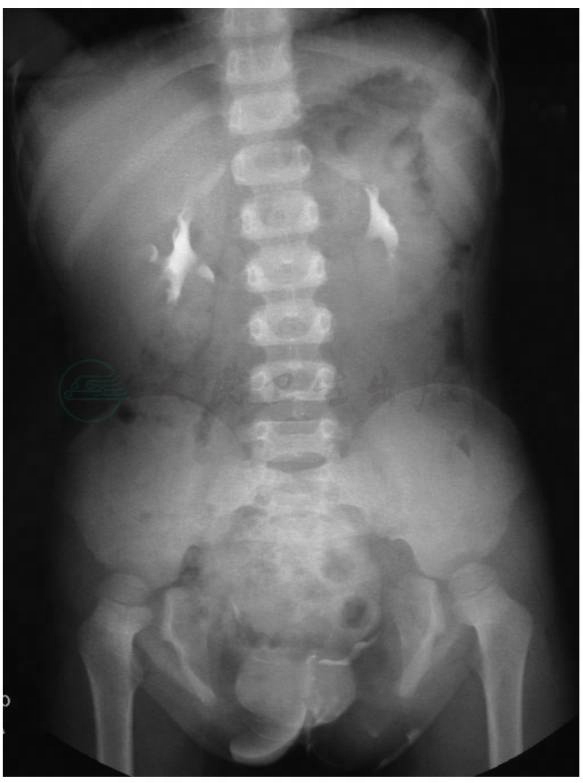

(2)做泌尿系超声、MR、静脉肾盂造影或者肾脏核素扫描,了解上尿路有无伴发畸形以及肾脏功能(图1)。

图1膀胱外翻IVP